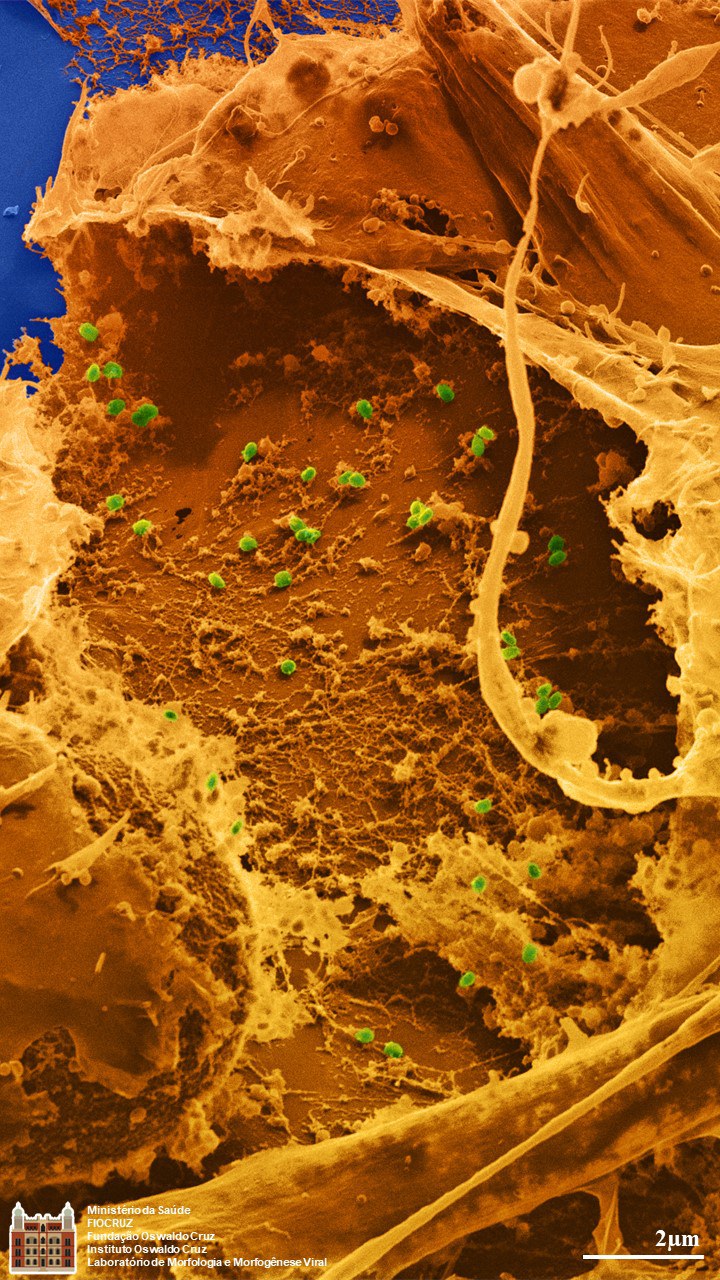

2º Lugar - Débora Ferreira Barreto Vieira: MPOX VIRUS

- MPOX VIRUS